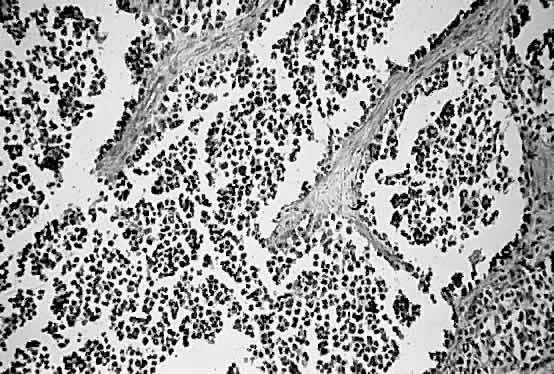

RMS was first reported in 1854 by Weber,50 but the conventional classification was developed by Horn and Enterline in 1958.51 The classification of Horn and Enterline describes four histologic variants of RMS: embryonal, botryoid, alveolar, and pleomorphic. Cross-striations (i.e., striated muscle differentiation) are seen only in approximately 60% of the lesions. Wilder's stain for reticulin may demonstrate the cross-striations more effectively.49 Electron microscopy49,52,53 (Fig. 2) and immunohistochemical staining for myosin, myoglobin, and desmin may also assist in the diagnosis of RMS subtypes.47,49 In addition, recent progress in molecular genetics may allow RMS to be diagnosed with the use of reverse transcriptase polymerase chain reaction and other modern techniques.24,25,47,54

Fig. 2. Electron micrograph of rhabdomyosarcoma demonstrating Z-bands within the cytoplasm of tumor cells. (Courtesy of R. Jean Campbell, MB, ChB, Mayo Clinic, Rochester, Minnesota.)

Embryonal RMS is the most common RMS type and usually occurs in the superonasal quadrant.7–9,13,34,49 The histologic features are characterized by a haphazard arrangement of spindle cells within a loose, myxoid stroma (Fig. 3).13,49,51 Botryoid RMS is considered a subtype of embryonal RMS; it usually occurs within the genitourinary tract or under mucosal membranes, such as the conjunctiva.2,13,49 The spindle cells in this variant are more densely organized.

Fig. 3. A. Rhabdomyosarcoma with spindle-shaped cells with a dense, interlacing pattern (H & E, × 160). B. Same specimen at a higher magnification. Note variation in size and shape of the spindle-shaped cells with a high density of nuclear chromatin (H & E, × 640). (Courtesy of R. Jean Campbell, MB, ChB, Mayo Clinic, Rochester, Minnesota.)

Alveolar RMS is the second most common type of RMS to involve the orbit and usually presents in the inferior quadrant.2,13,49 Its histologic pattern resembles the architecture of alveolar tissue of the lung (Fig. 4). The prognosis of alveolar RMS is considered worse than that of the embryonal variant.

Fig. 4. Alveolar pattern of rhabdomyosarcoma (H&E, × 90). (Courtesy of R. Jean Campbell, MB, ChB, Mayo Clinic, Rochester, Minnesota.)